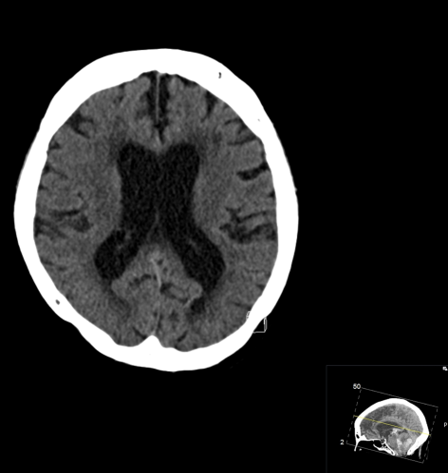

CASE 2 -A 54-year-old man walks into emergency 3 hours after a 150kg plank of wood fell on his head. He has obvious external signs of head injury and a cracking headache, however, neurologically he is intact. A CT head scan is performed

EXPLANATION –There is a depressed right parietal bone fracture with underlying pneumocephalus (indicates an open skull fracture) and a small subdural hematoma.

- Overlying this there is a scalp hematoma.

- There is also a non-displaced fracture in the frontal bone. This fracture crosses the midline and probably has injured the anterior aspect of the superior sagittal sinus.

- Tears of the dural venous sinuses may cause an extradural hematoma (EDH), as in this case. The hematoma is seen external to the compressed superior sagittal sinus.

Extradural bleeds (EDH) are located between the outer layer of dura and endosteal layer of skull. Like in this case, they are usually associated with calvarial fractures.

- They typically demonstrate biconvex or lentiform shape and are limited by sutures as periosteum is attached at the sutures limiting spread of the bleed.

- The source of bleed is arterial in origin, from a middle meningeal artery as opposed to venous in subdural bleeds.

- Up to 10% of EDH are due to venous bleeding, follow the laceration of a dural venous sinus, as we see in this case.

- There is often displacement of the sinus away from the underlying bone. There are three locations characteristic of venous EDH; the vertex, anterior middle cranial fossa and the occipital posterior fossa.

- Hypodense areas within a bleed likely represent unclotted blood suggesting active bleeding.

- As these bleeds are venous, there is not the same urgency for decompression in theatre. In fact, this patient was managed conservatively as operative intervention poses a risk of further damage to the venous sinuses.